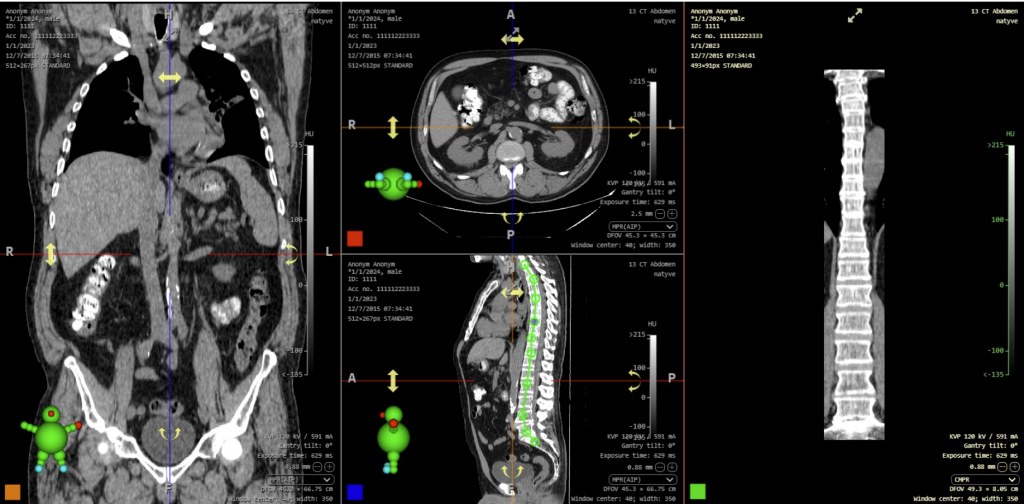

- Support for RTSTRUCT display with the “Load RT Struct” function, it is now possible to display Radiotherapy Structure (RTS) modality data, for example, a radiotherapy plan over a series of CT modality images. This function is called up by right-clicking on the RTS data displayed in the working set of images to bring up the context menu and then selecting the “Load RT Struct” action.